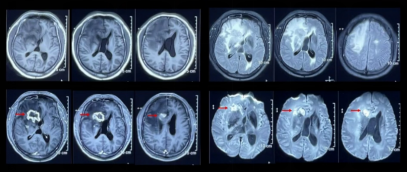

又过了半年,在2020年11月,患者日间睡眠增多,MRI发现左侧额叶,环形强化、占位效应、弥散受限(图5),与2019年11月的结果有着惊人的相似,依然是额叶病灶,只是由一年前的右侧变为了左侧……

图5:左侧额叶,环形强化、占位效应、弥散受限

查头颅核磁,发现在激素冲击治疗后,病灶持续进展,不仅临床表现上新出现左下肢力弱,MRI上也出现双额叶白质多发环形强化病灶。